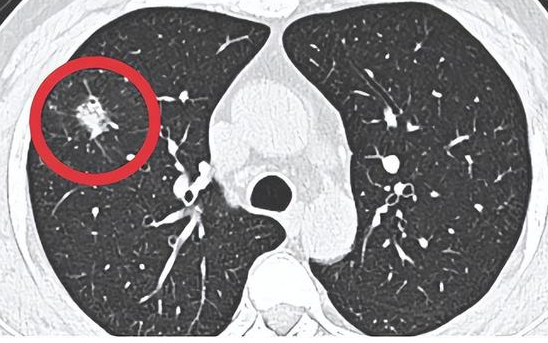

肺部结节的性质一般通过肺部结节在CT上的形状、大小、边界、钙化和CT值来评估。

典型的肺部原发性恶性结节有许多CT症状,如分叶状或放射状骨针状、密度不均匀、靠近胸膜的胸膜凹陷等。结节越大越孤立,就越有可能是恶性的。良性结节的特点是清晰、规则、边缘光滑,密度均匀,无胸膜牵拉。